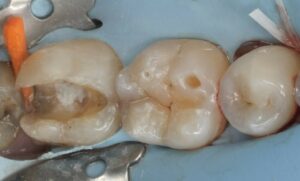

Abbildung 3: Direkte Überkappung der eröffneten Pulpa an Zahn 37 mit MTA vpt am zentralen Kavitätenboden.